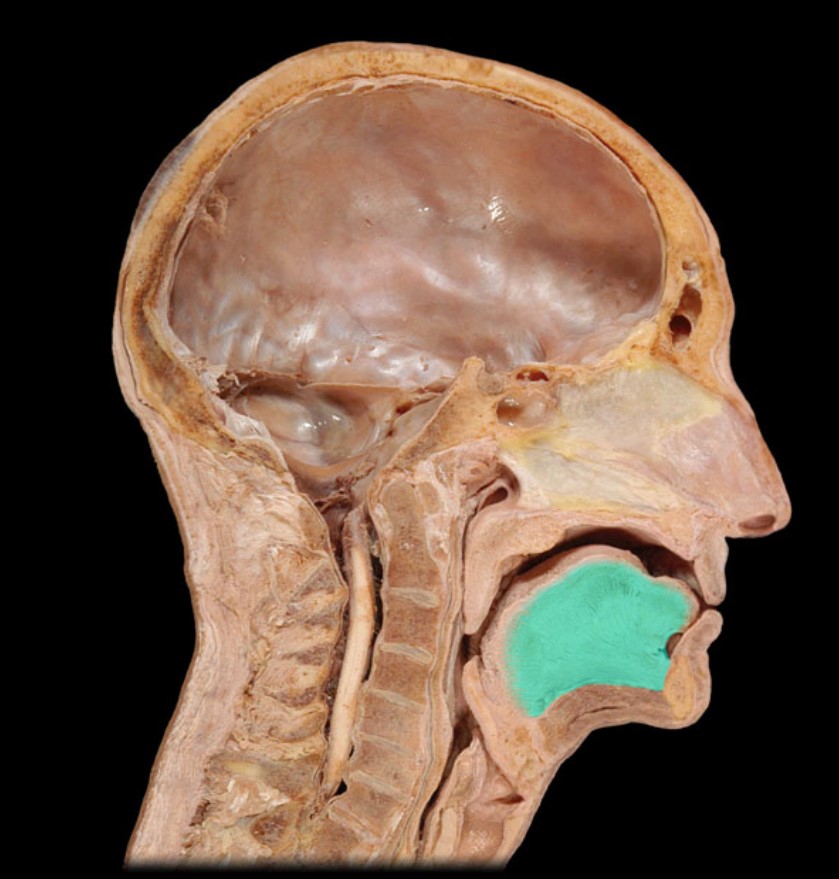

Esophagus

Trachea

Vocal Fold

Epiglottis

Hyoid

Mandible

Mylohyoid

Geniohyoid

Genioglossus

Lingual Tonsil

Palatine Tonsil

Uvula

Soft Palate

Palatine Bone

Maxilla

Pharyngeal Tonsil

Auditory Hiatus

Torus Tubarius

Sphenoid Sinus

Inferior Nasal Concha

Middle Nasal Concha

Superior Nasal Concha

Nasal Vestibule

External Nares

Frontal Sinus